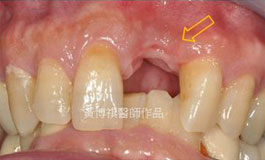

前後比較: |